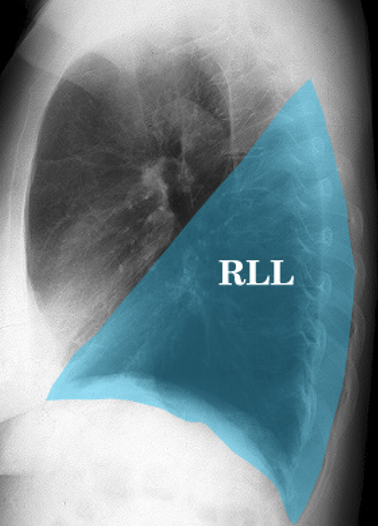

What lobe of the right lung is located primarily posteriorly?

A

Right Lower Lobe (RLL)

Q

How high up posteriorly will the RLL extend?

T6